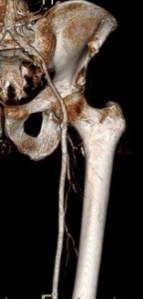

When conduit is limited, or PTFE or cadaver vein is being considered, in the setting of occluded SFA stents, I have found that it is possible and perhaps preferable to attempt removal of these stents using remote endarterectomy.

The CTA, particularly with 3D reconstruction, is helpful in planning these cases.

The additional material needed is fluoroscopy and endovascular skills. Directing a subintimal Glidewire helps free the stent and aid passage of the Moll ring dissector.

Adding cold saline seems to help shrink the stents. A plaque free distal end point allow the stents to be removed with a gentle tug.

I put these patients on coumadin anticoagulation. Surveillance is needed for recurrent stenoses -typically these occur randomly as focal TASC A stenoses, and likely represent remnant medial tissues that have caused intimal hyperplasia. This may be particularly amenable to treatment with drug eluting balloons. Failure as thrombosis typically is limited to the treated vessel without the embolism seen when PTFE grafts fail. Failure tends to occur in smokers. Inability to pass the dissector is usually seen in patients with heavy calcification -diabetics, renal failure, and I would avoid attempting remote endarterectomy in these patients. When the dissectors fail to pass, cutting down and directly endarterectomizing the vessel and resuming remote endarterectomy is feasible. The common femoral artery is repaired with a patch. I try to avoid having to place a distal stent and when a tapered end point, as in a successful carotid endarterectomy, is achieved, usually unnecessary.